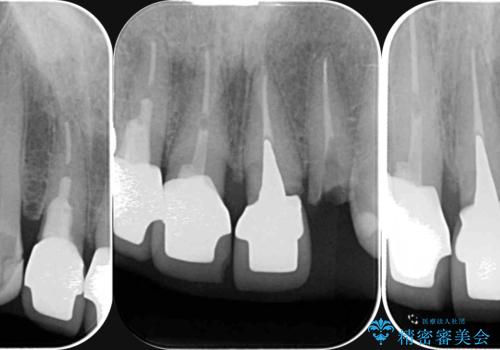

X線検査・視診より強くぶつけた前歯は折れてしまい、抜歯が必要な状況です。

抜歯後の見た目改善として深い咬合関係であることからインプラントは避け、ブリッジで補綴治療を行っていくこととしました。

元々の噛み合わせが深く(ディープバイト)、転んで顎を強打したことで上顎前歯2本が根元から折れてしまい抜歯をしなければいけない状況となってしまいました。